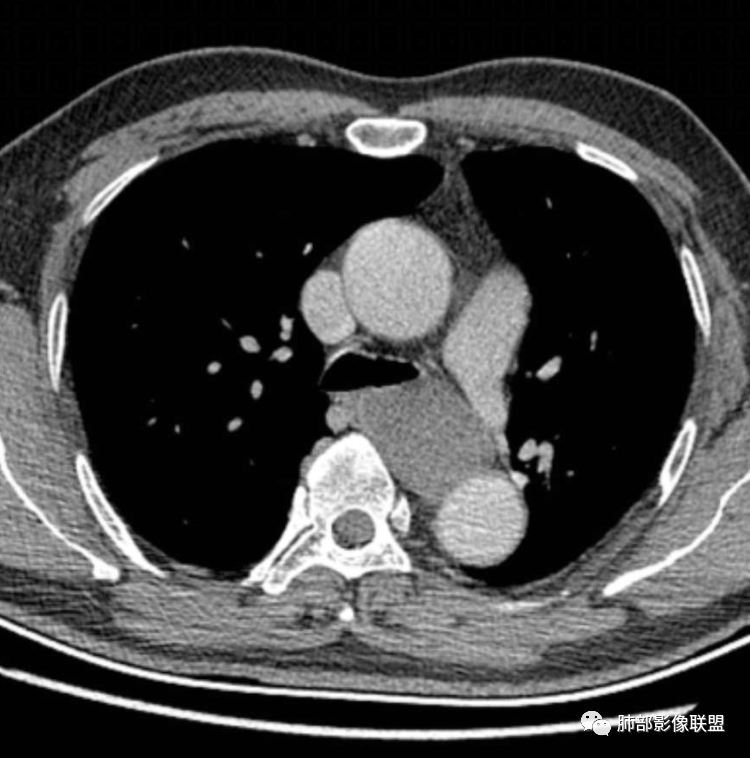

患者,男,43岁,无意间发现纵隔肿物,无胸闷胸痛,无心慌气短,无咳嗽,无吞咽困难等不适。体检发现的,无症状。

气管、左主支气管后方,食道左侧囊性占位,壁薄且均匀、光滑。气管及左主支气管受压凹陷、变形。

食道也受压变形、移位。